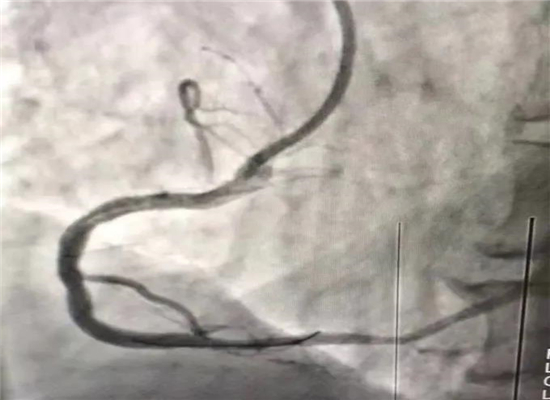

介入手术后